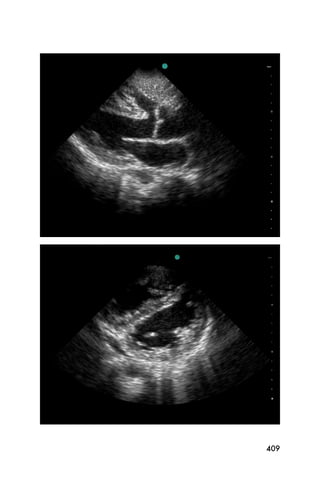

Figure 12. Apical four view showing the right (RV) and left (LV)

ventricles, and the right (RA) and left (LA) atria

In this view, the ventricles are noted on the right of the

screen and the atria on the left. Figure 15 shows an

ultrasound image of the heart from a subxyphoid view.

Figure 15. Subxyphoid view showing the liver as an acoustic window,

the right ventricle (RV), left ventricle (LV) and atria (RA and LA)